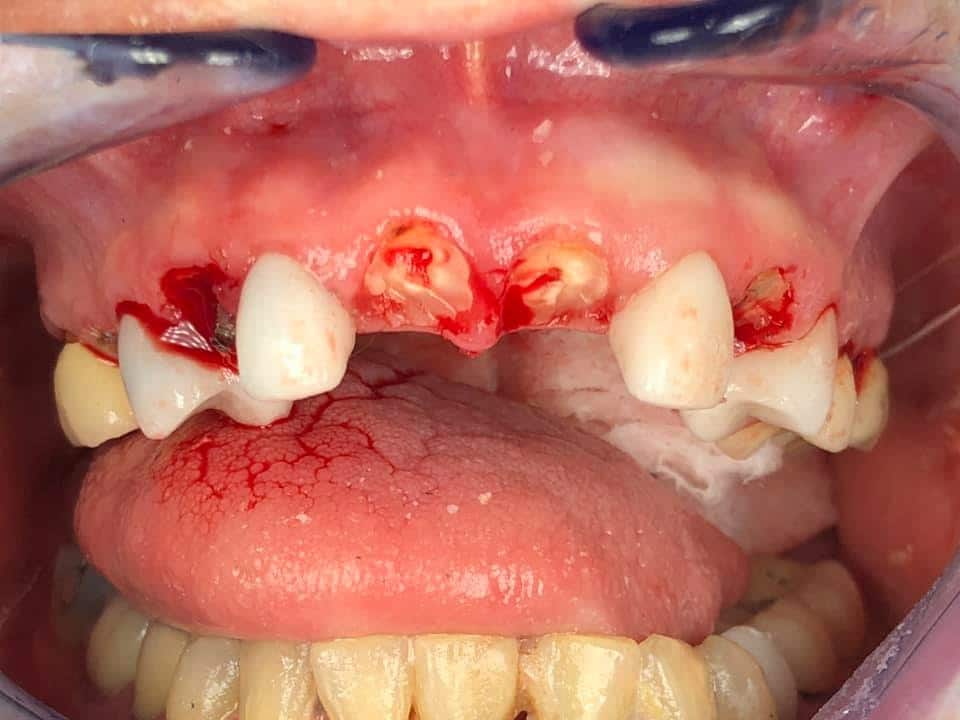

Below is a case of full arch same day temporization using the socket shield , root submergence and pontic shield techniques to preserve the site architecture . Neodent GM implants were placed in a guided fashion and same day temporization was performed using a milled PMMA.